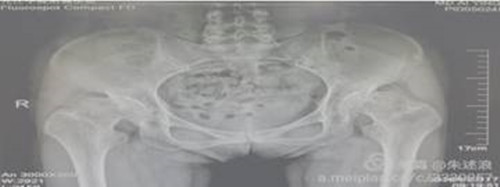

患者二十余年前开始出现髋关节疼痛,行走后疼痛加重,进行理疗、药物等保守治疗无明显效果,七个月前来临床医学院/附属医院就诊,行盆骨平片检查提示“双侧髋关节半脱位,股骨头缺血性坏死”。临床医学院/附属医院骨三科朱述浪主任带领手术团队为患者实施DAA微创手术,手术非常成功,患者在术后次日便能够负重行走,并保留正常的步态。